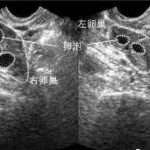

女性生育的合适年龄是22岁到30岁,一般来说,35岁之前试管婴儿的成功率较高。生殖科医生会建议育龄夫妇考虑在女方35岁之前生育。一方面,35岁之前的女性卵巢储备功能较好,怀孕的概率较高。另一方面,孕期面临的妊娠高血压、流产率等风险较低。为什么年龄在生育中发挥着重要作用?一个原因是女性在老年时排卵的频率很低。另一个原因是她们会出现很多不孕疾病,例如子宫内膜异位症。但更重要的是女性卵子质量下降和数量减少。更多的卵子会导致染色体异常,从而流产。

35岁相当于女性生育能力的一个分水岭。35岁以后,女性卵巢储备功能会逐渐下降,卵泡数量减少,性激素的变化,月经周期的改变等。这些都表明生育率在下降。所以即使做试管婴儿,成功率也低于年轻患者。对于35岁以上的女性,如果打算做试管婴儿,宜早不宜迟。因为卵巢储备功能在变化,越早做试管婴儿。高龄女性的生育力下降是不容置疑的,因为第一次生育年龄越来越晚,考虑过多的人。胚胎因此,卵巢储备功能下降的患者比例每年都在增加。控制性促排卵术中排卵抑制作用的女性卵巢反应降低的比例显着提高。据估计,5%至18%的试管周期是由卵巢反应减弱结束的。卵巢反应不良会导致卵泡数量减少,产卵质量降低,尤其是优质卵子的供应不足。周期取消率高,妊娠率严重下降已成为辅助生殖领域的一个问题.